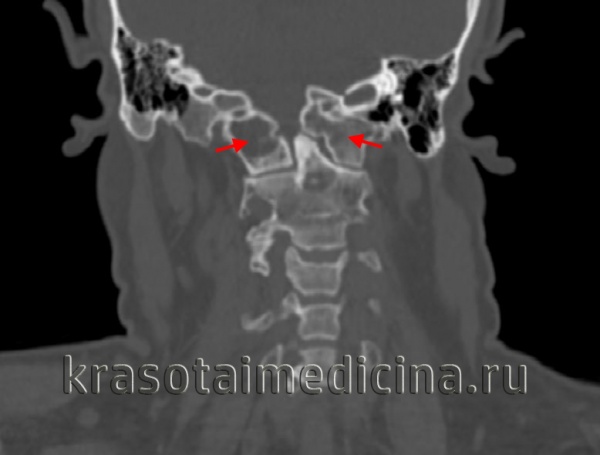

(Слева) На аксиальной КТ в костном окне определяются большие срединные костные дефекты передней и задней дуги С1. Широкие щели свидетельствуют о нестабильности.

(Справа) На корональной КТ в костном окне на фоне врожденного сколиоза определяются распространенные нарушения сегментации шейных и грудных позвонков. Боковые массы С1 независимо смещены кнаружи в противоположных направлениях (расщепление атланта). Такая конфигурация крайне нестабильна и требуется спондилодез.

(Справа) На сагиттальном КТ-срезе пациента с расщеплением кольца С1 видны умеренно диспластичный зубовидный отросток и признаки гипоплазии кольца С1, являющиеся причиной тяжелого стеноза спинномозгового канала. Обратите внимание на сочетанное нарушение сегментации С2/3. (Слева) На аксиальном КТ-срезе определяется широкий срединный костный дефект передней и задней дуг атланта. Такой широкий дефект позволяет предположить наличие нестабильности.

(Справа) На фронтальном КТ-срезе представлен случай врожденной сколиотической деформации и распространенной аномалии сегментации шейно-грудного отдела позвоночника. Боковые массы С1 независимо друг от друга смещены в противоположных направлениях, что обусловлено расщеплением атланта у данного пациента. Это очень нестабильный тип аномалии, требующий хирургической стабилизации.